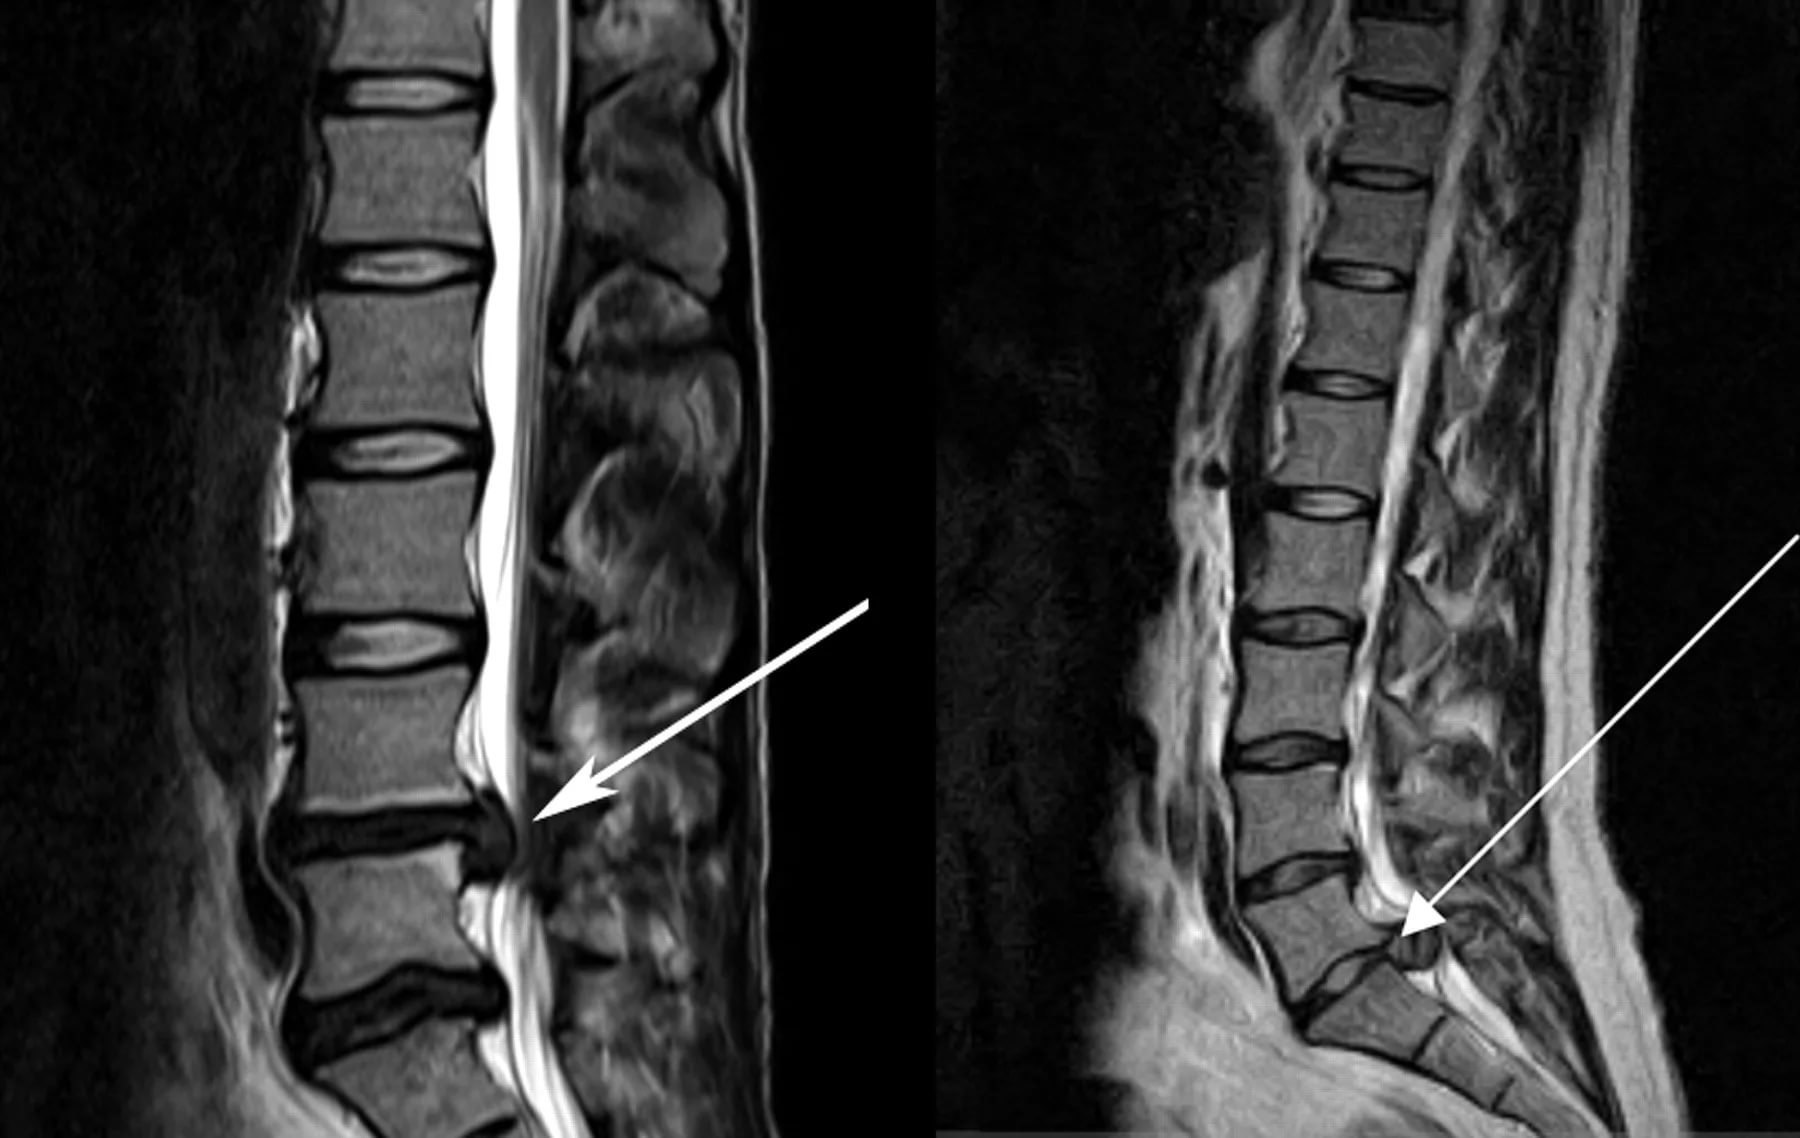

Миелография с контрастом — видны поврежденные участки

Определить причину боли в пояснице из-за долгого нахождения в стоячем положении можно по результатам комплексной диагностики. Может понадобиться проведение следующих мероприятий:

• Миело(томо)графия. Контрастное вещество вводят в субарахноидальное пространство для визуализации спинного мозга и определения проходимости.

Для выявления различной этиологии новообразований в спинном мозге, позвоночнике, мягких тканях проводят магнитно-резонансную и компьютерную томографию.